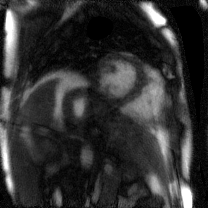

Supervised Deep-Learning (DL)-based reconstruction algorithms have shown state-of-the-art results for highly-undersampled dynamic Magnetic Resonance Imaging (MRI) reconstruction. However, the requirement of excessive high-quality ground-truth data hinders their applications due to the generalization problem. Recently, Implicit Neural Representation (INR) has appeared as a powerful DL-based tool for solving the inverse problem by characterizing the attributes of a signal as a continuous function of corresponding coordinates in an unsupervised manner. In this work, we proposed an INR-based method to improve dynamic MRI reconstruction from highly undersampled k-space data, which only takes spatiotemporal coordinates as inputs. Specifically, the proposed INR represents the dynamic MRI images as an implicit function and encodes them into neural networks. The weights of the network are learned from sparsely-acquired (k, t)-space data itself only, without external training datasets or prior images. Benefiting from the strong implicit continuity regularization of INR together with explicit regularization for low-rankness and sparsity, our proposed method outperforms the compared scan-specific methods at various acceleration factors. E.g., experiments on retrospective cardiac cine datasets show an improvement of 5.5 ~ 7.1 dB in PSNR for extremely high accelerations (up to 41.6-fold). The high-quality and inner continuity of the images provided by INR has great potential to further improve the spatiotemporal resolution of dynamic MRI, without the need of any training data.